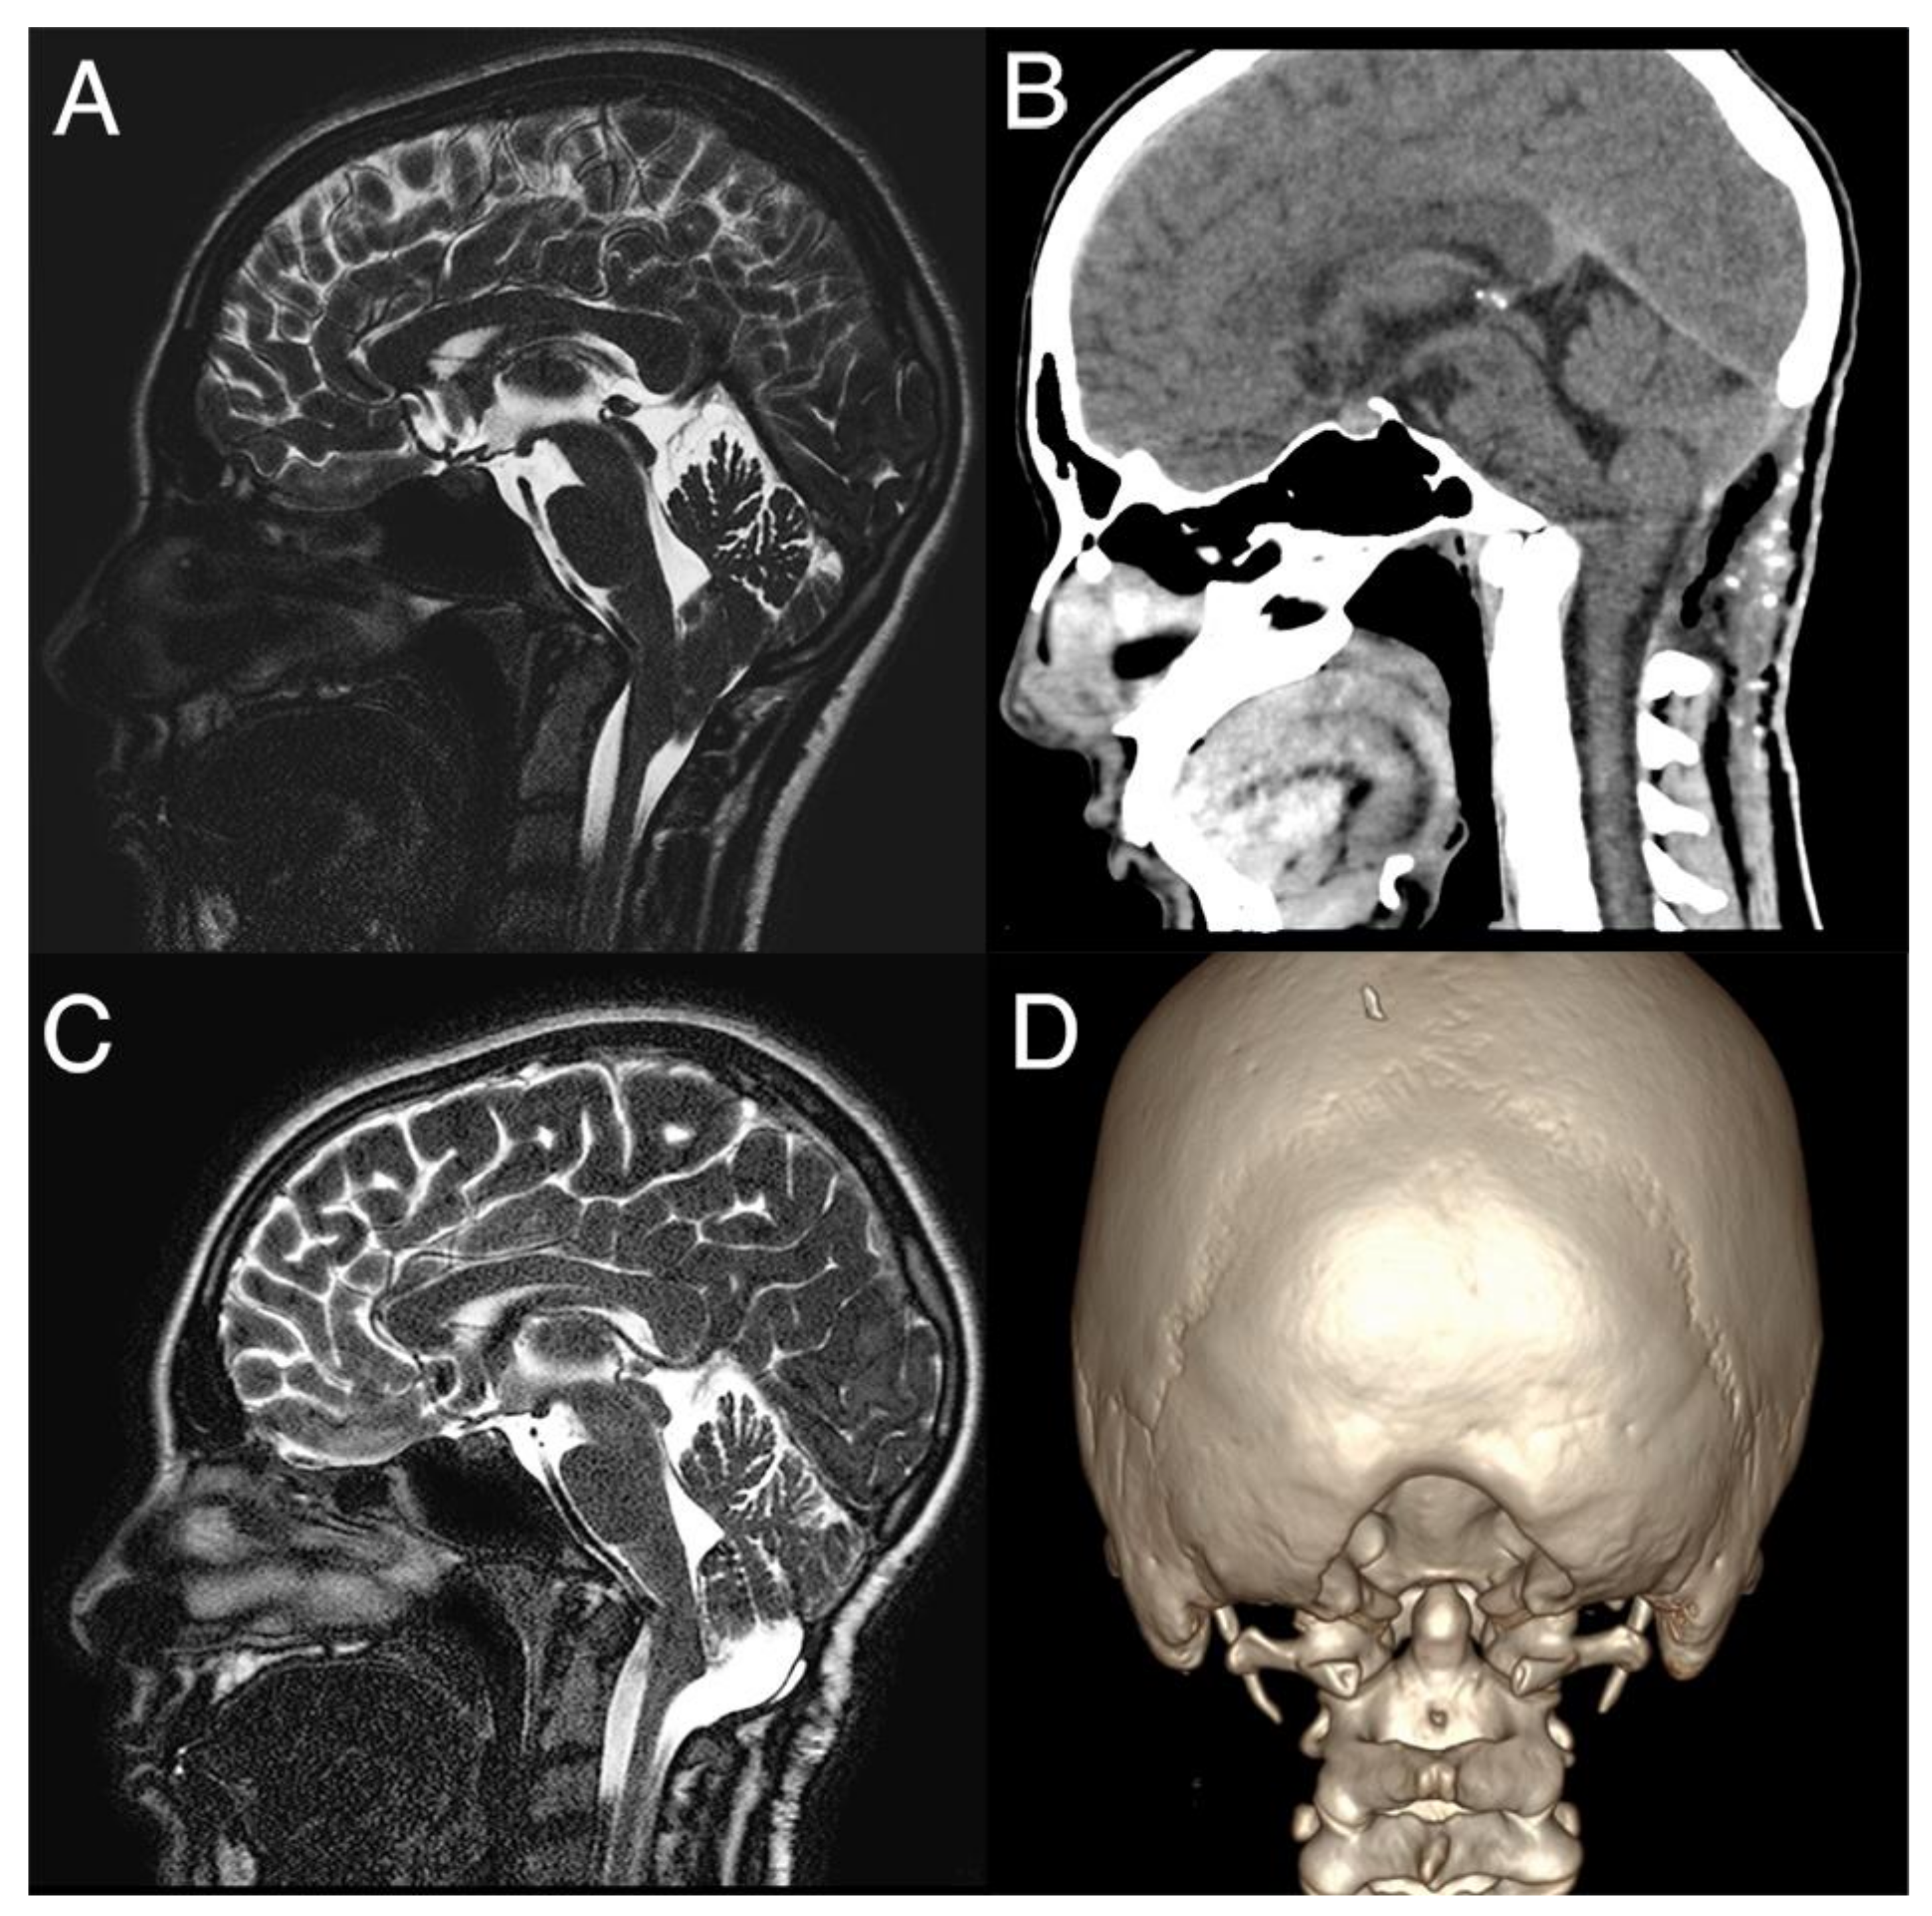

All children underwent PFDD and C1 laminectomy (Figure 1).

Figure 1. Chiari 1.5 malformation: the preoperative T2-weighted mid-sagittal scan demonstrates the displacement of the cerebellar tonsils and hindbrain below the foramen magnum (A). The patient was submitted to PFDD: the postoperative CT scan (B) with 3D reconstruction (coronal view in (D)) showed the entity of bony decompression, with CSF flow in the posterior fossa and reduction of tonsil descent (C).